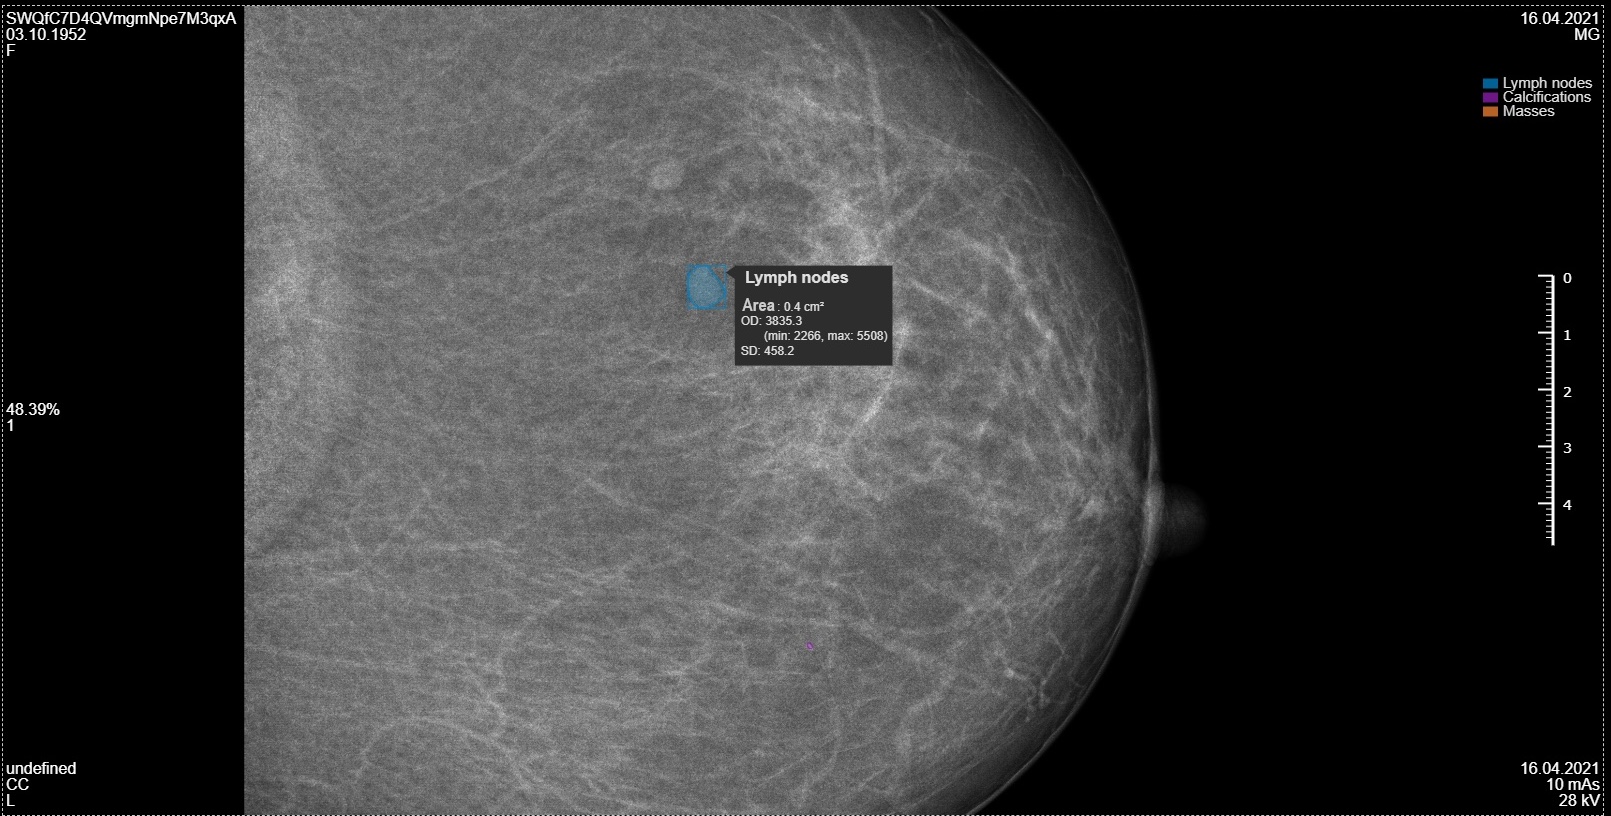

• Localizes pathologies with precise visual annotations on native mammogram images

• Performs quantitative analysis of detected elements, including their number and area